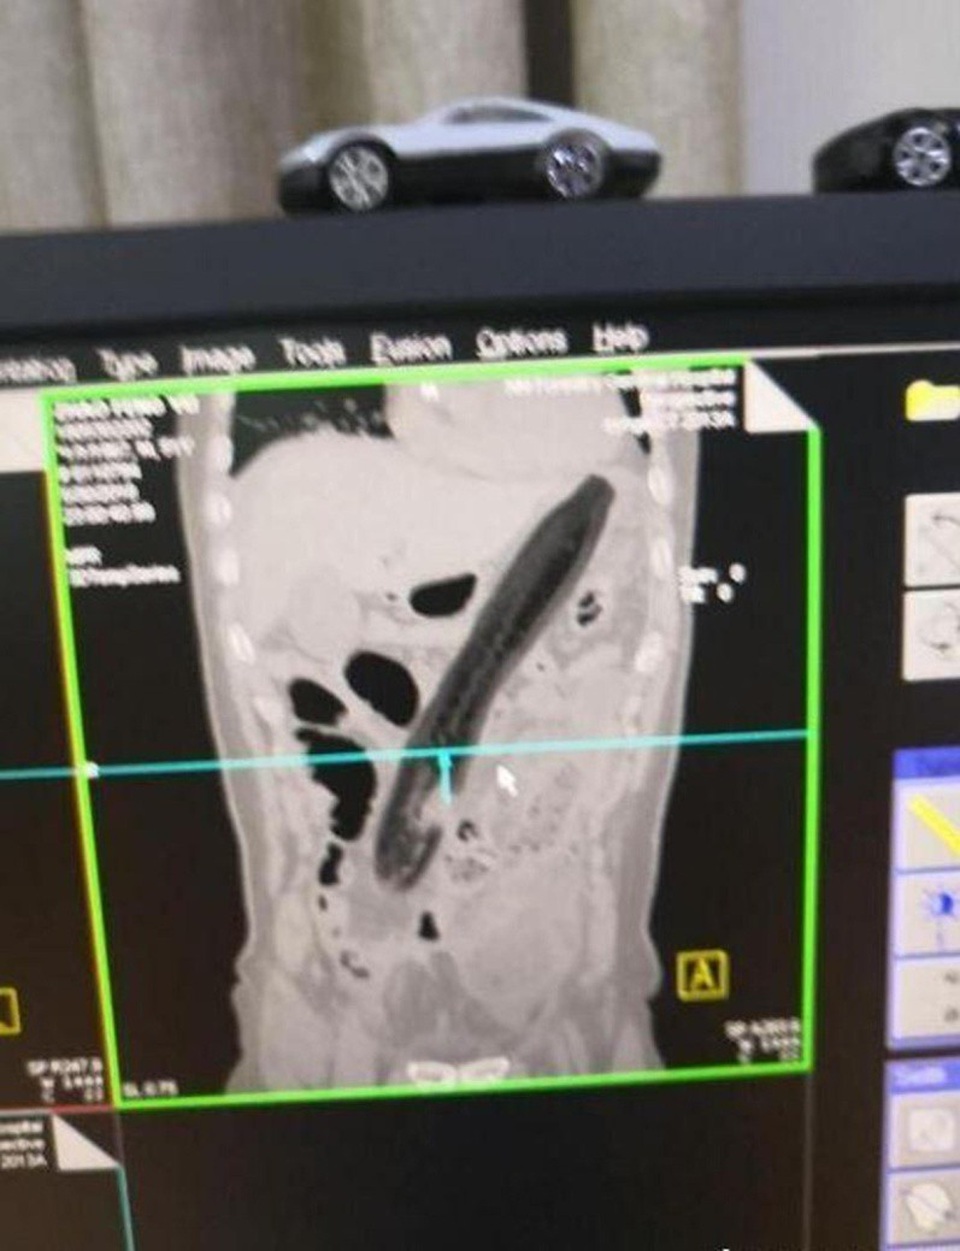

Hình ảnh chụp X quang cho thấy quả cà tím nằm nguyên vẹn trong ruột của bệnh nhân và anh ta phải trải qua phẫu thuật để lấy nó ra. Báo Kan Kan còn cho biết bệnh nhân đã nghĩ rằng trái cây mà cụ thể là quả cà có thể giúp mình trị chứng táo bón.